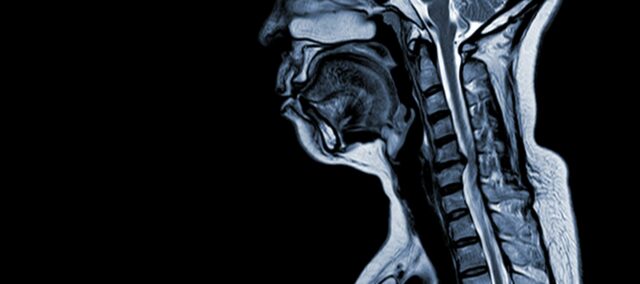

โรคไขสันหลังส่วนคอเสื่อม (CSM) เป็นภาวะทางระบบประสาทที่เป็นสาเหตุหลักของการบาดเจ็บที่ไขสันหลังในผู้ใหญ่ หากอธิบายแบบง่ายๆ ก็คือเกี่ยวข้องกับการบีบอัดหรือความเสียหายของไขสันหลังบริเวณคอ ซึ่งเกิดจากกระบวนการชราตามธรรมชาติที่ส่งผลต่อกระดูกสันหลังส่วนคอเป็นหลัก คำว่า ‘myelopathy’ มาจากคำภาษากรีก ‘myelon’ ซึ่งแปลว่า ‘ไขสันหลัง’ และ ‘pathos’ ซึ่งแปลว่า ‘โรค’

- หมอนรองกระดูกเสื่อม (หมอนรองกระดูกโป่งพอง) : CSM มักเริ่มต้นด้วยการเสื่อมของหมอนรองกระดูกสันหลังบริเวณกระดูกสันหลังส่วนคอ ทำให้หมอนรองกระดูกสันหลังปลิ้นหรือยื่นเข้าไปในช่องกระดูกสันหลัง

- การก่อตัวของกระดูกใต้เยื่อหุ้มกระดูก (ช่องด้านท้องถึงช่องกระดูกสันหลัง) : เพื่อตอบสนองต่อความเครียดทางกลที่เพิ่มมากขึ้น ร่างกายจะสร้างเนื้อเยื่อกระดูกใหม่ที่ด้านหน้า (ด้านท้อง) ของช่องกระดูกสันหลัง ซึ่งอาจทำให้ช่องว่างสำหรับไขสันหลังแคบลง

- การเกิดกระดูกของเอ็นตามยาวด้านหลัง: เอ็นตามยาวด้านหลังอาจมีการสร้างกระดูก แข็งตัว และมีแคลเซียมเกาะ ส่งผลให้ช่องกระดูกสันหลังแคบลง

- การเจริญเติบโตมากเกินไปของ Ligamentum Flavum: การหนาตัวของเอ็น Flavum ทำให้เอ็นหนาขึ้นและยืดหยุ่นน้อยลง ส่งผลให้เข้าไปในช่องว่างระหว่างช่องกระดูกสันหลังมากขึ้นและกดทับไขสันหลัง

การเปลี่ยนแปลงโครงสร้างเหล่านี้รวมกันทำให้เกิดการกดทับและการตีบแคบของช่องกระดูกสันหลัง ส่งผลให้เกิดอาการเด่นและภาวะแทรกซ้อนที่เกี่ยวข้องกับ CSM การรับรู้ปัจจัยเสี่ยงเหล่านี้และการทำความเข้าใจกลไกทางพยาธิสรีรวิทยาที่เกี่ยวข้องถือเป็นสิ่งสำคัญทั้งในการป้องกันและการจัดการ การวินิจฉัยในระยะเริ่มแรกและการแทรกแซงที่เหมาะสมเป็นสิ่งสำคัญในการบรรเทาผลกระทบของการเปลี่ยนแปลงโครงสร้างเหล่านี้ต่อไขสันหลัง